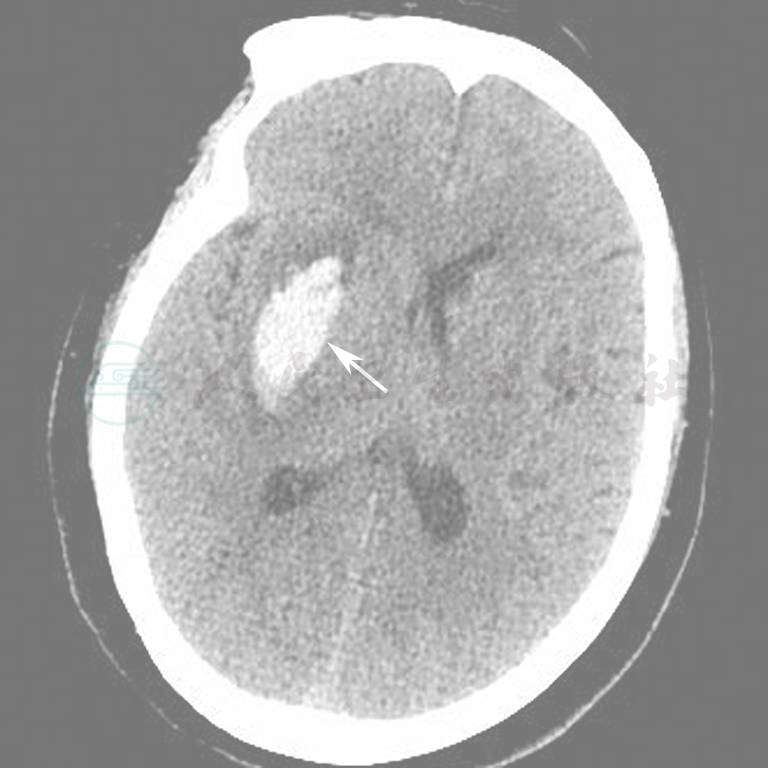

图8  右侧基底节区脑出血

图9  脑干右份出血

图10  颅内出血(硬膜外)

图11  双侧颅内出血(硬膜下)